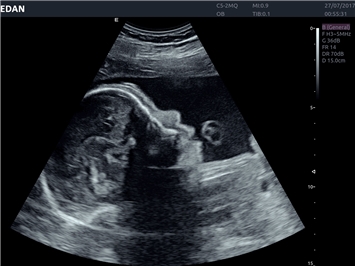

• Автоматизированные измерения в акушерстве

• Акушерства и гинекологии

Гинекология:

Да